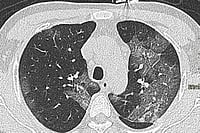

The body does try to fight back the viral invasion and Covid-19 seems to be a mild disease in most infected people. However, the loss of ACE2 shifts the balance towards higher and uncontrolled Angiotensin II and can make things go haywire. Indeed, higher levels of Angiotensin II increases vascular permeability in the lungs of many Covid-19 patients. The unbridled inflammation and oxidative stress (i.e. damage due to uncontrolled production of ROS) induced by hyperactive Angiotensin II can also fuel a vicious loop of damage to alveolar cells and pulmonary capillaries, hyperplasia (i.e. pathological increase of cell size) of the alveolar cells, formation of aberrant hyaline membranes and thick fibrosis in the damaged zones. WBCs crowd at these damaged sites, leading to more inflammation and further tissue damage. The clinical result is pulmonary edema and ARDS, a common state in Covid-19 emergencies.

Cardiac tissue can be subjected to a similar battering. Up to 28% of hospitalised cases suffer cardiac injury. SARS-CoV-2 could invade pericytes and the endothelial cells of capillaries in the heart, leading to micro-circulation disorders. Increased myocardial fibrosis, myocarditis (i.e. inflammation of heart muscles), cardiac arrhythmias, acute cardiac injury and cell death are not uncommon. Furthermore, the downregulation of ACE2 unleashes inflammation which, in turn, raises blood pressure—an extra load on the already-weakened cardiac system. Heart diseases that were under control can suddenly become unmanageable post-Covid. As the infection radiates out, the virus directly targets the kidney, especially the specialised cells of the renal tubular epithelium. The renal blood vessels are also attacked, and this can induce Acute Kidney Injury. There is also growing evidence that the testes are affected and a link with brain damage is being reported. Unless stopped, Covid-19 rages towards multi-organ damage.